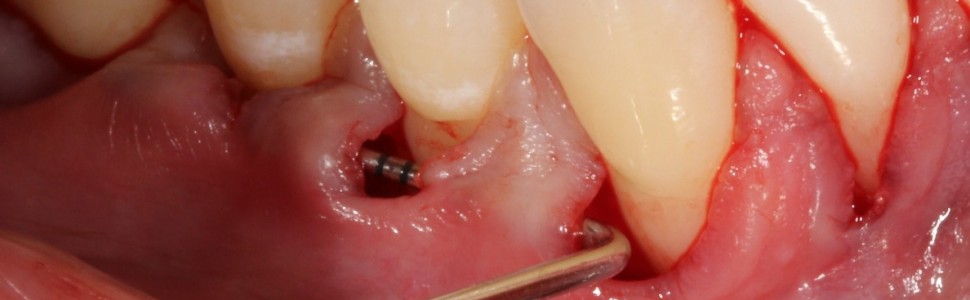

Pokrycie mnogich recesji dziąsłowych całego łuku zębowego na jednej wizycie zmodyfikowaną techniką tunelową z zastosowaniem podnabłonkowej tkanki łącznej oraz białek matrycy szkliwa (EMD). Opis przypadków

Covering multiple adjacent recessions of the entire dental arch in one visit with a modified tunneling technique using subepithelial connective tissue and enamel matrix proteins (EMD). Case study

Chirurgiczne leczenie mnogich recesji dziąsłowych jest wymagającym klinicznie zabiegiem ze względu na duże pole zabiegowe, różne ustawienie poszczególnych zębów w łuku (często ich znaczne doprzedsionkowe wychylenie), różne wymiary recesji przy każdym zębie, cienki fenotyp i wąską strefę dziąsła skeratynizowanego lub jej brak przy wielu zębach. Optymalnym postępowaniem w leczeniu mnogich recesji może być zabieg chirurgiczny przy wszystkich zębach w łuku na jednej wizycie. Czas zabiegu jest dłuższy, ale pacjent nie musi kilkakrotnie powtarzać zabiegów oraz ponownie stosować farmakoterapii i zaleceń pozabiegowych. Celem pracy było przedstawienie zabiegów pokrycia mnogich recesji dziąsłowych po stronie prawej i lewej łuku zębowego podczas jednej wizyty. Zabiegi przeprowadzono z wykorzystaniem zmodyfikowanej techniki tunelowej i przeszczepu podnabłonkowej tkanki łącznej, dodatkowo stosując białka pochodne matrycy szkliwa w miejscu biorczym.

The treatment of multiple adjacent recession appears to be more challenging for the clinician due to large surgical field, variation in teeth position in the dental arch (prominent roots), variation in recession size, thin phenotype and insufficient keratinized tissue in many teeth. Surgical treatment of all multiple recessions in one dental arch during one session appears to be optimum. Surgical treatment time is longer, however patients don’t need to undergo multiple surgeries, pharmacological therapies and postsurgical instructions. The aim of this article was to present surgical treatment of multiple adjacent gingival recessions with the use of modified tunnel technique, subepithelial connective tissue graft and enamel matrix protein derivatives during one session.